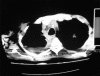

Subcutaneous emphysema in cavitary pulmonary tuberculosis without pneumothorax or pneumomediastinum

Extra-alveolar air in the form of subcutaneous tissue emphysema is observed in a variety of clinical settings. Spontaneous subcutaneous emphysema in the absence of pneumothorax or pneumomediastinum is very rare. We report a case of spontaneous subcutaneous emphysema secondary to cavitary pulmonary tuberculosis in the absence of pneumothorax or pneumomediastinum.